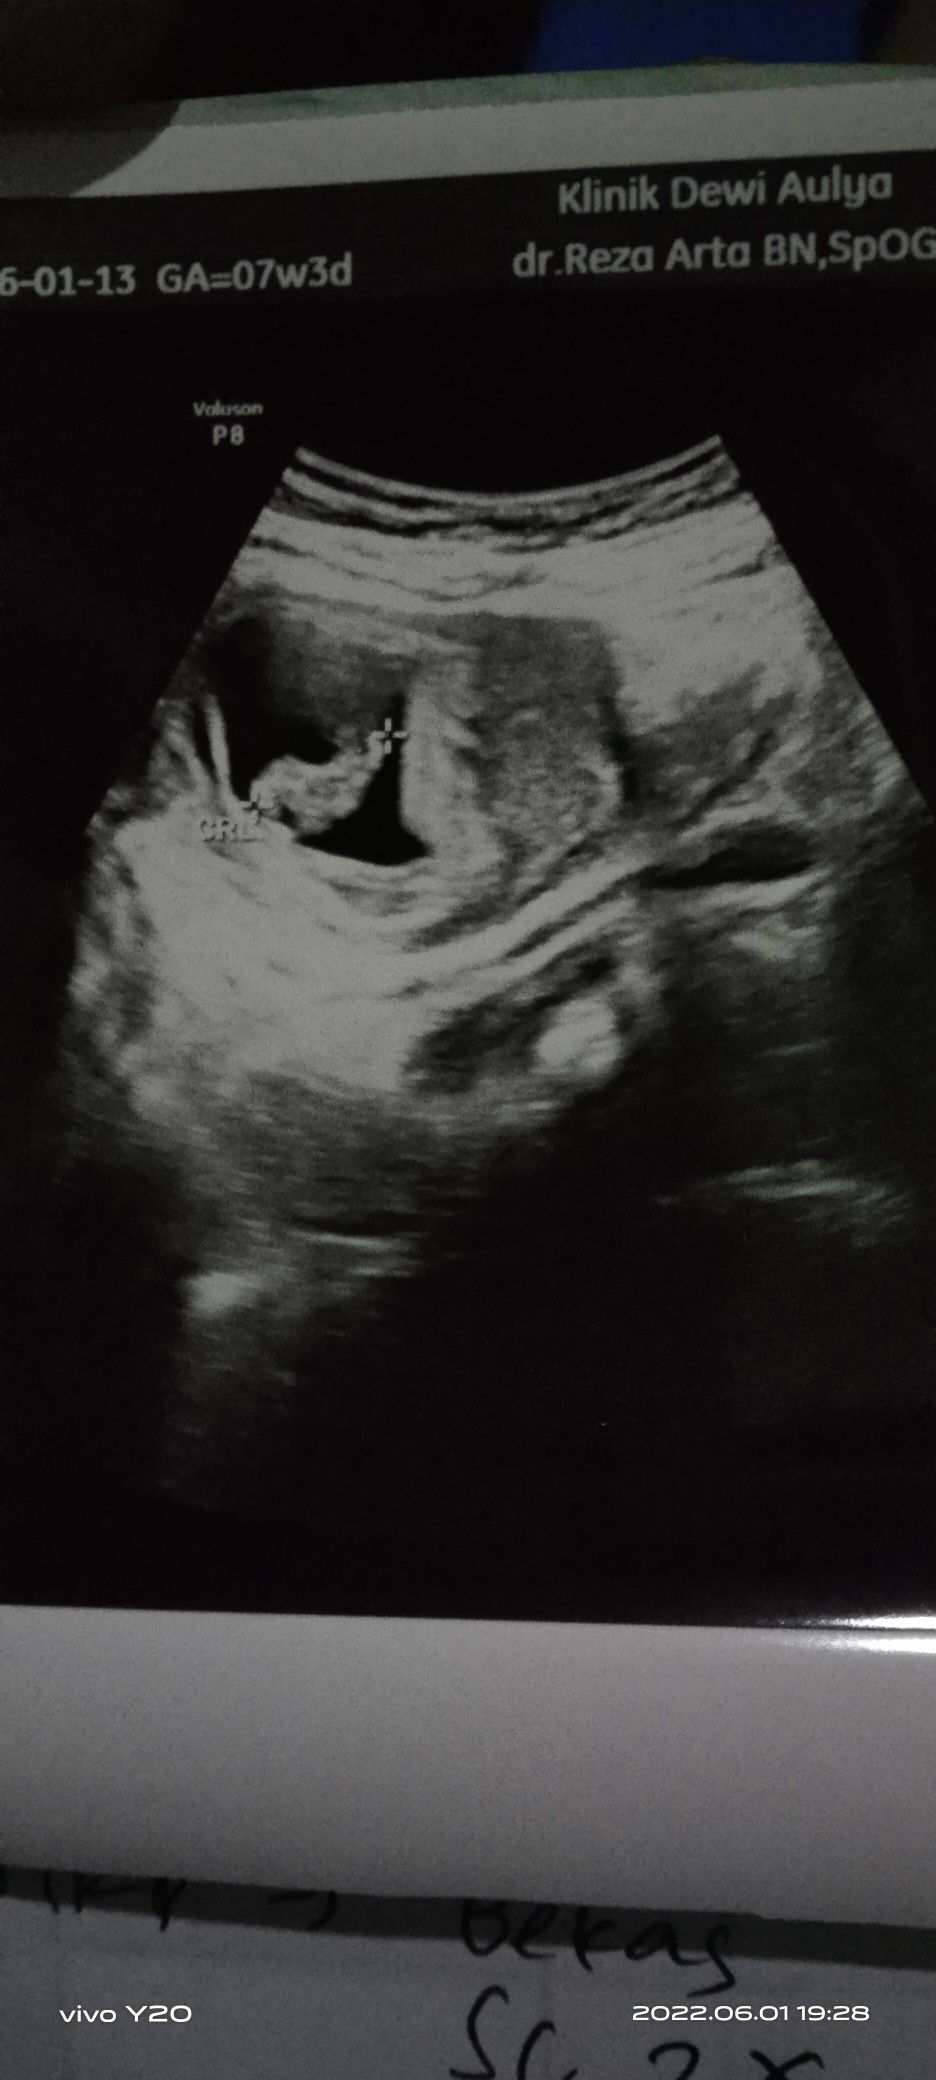

aku hpl 18 Januari diusg 20 Januari